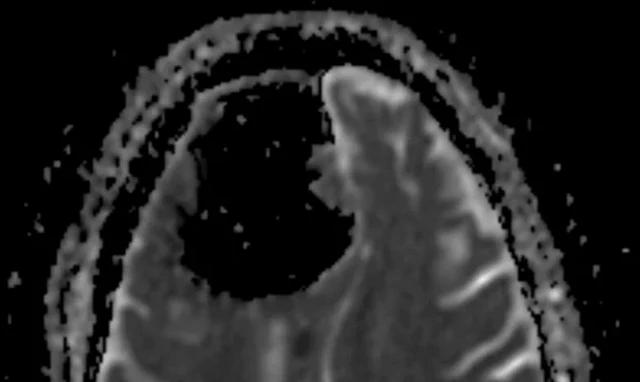

หลังทำการตรวจด้วยเครื่องเอกซเรย์คอมพิวเตอร์ (CT Scan) และเครื่องตรวจเอ็มอาร์ไอ (MRI) แพทย์ต้องตกตะลึง เมื่อพบโพรงอากาศขนาดใหญ่ในสมองกลีบหน้าด้านขวาของคนไข้ผู้นี้ ซึ่งวินิจฉัยแล้วน่าจะเกิดจากเนื้องอกในกระดูกชนิดที่ไม่เป็นอันตรายค่อย ๆ โตขึ้นในโพรงไซนัสหรือโพรงอากาศข้างจมูก และไปสร้างแรงกดกับฐานกะโหลกศีรษะ จนกระดูกบริเวณที่ติดกับโพรงจมูกเกิดการกร่อนตัวและปล่อยให้อากาศรั่วซึมเข้าไปสะสมในสมองโดยไม่อาจไหลกลับออกมาได้

"เมื่อแรงดันอากาศเพิ่มขึ้น เนื้อสมองจึงถูกเบียดให้ไปกองรวมกันอยู่อีกด้านหนึ่ง แพทย์อาจผ่าตัดแก้ไขภาวะนี้ได้ แต่ก็ออกจะเสี่ยงเกินไปและมีอันตรายมาก ทำให้คนไข้ผู้นี้ตัดสินใจไม่รับการผ่าตัด" นายแพทย์บราวน์กล่าว